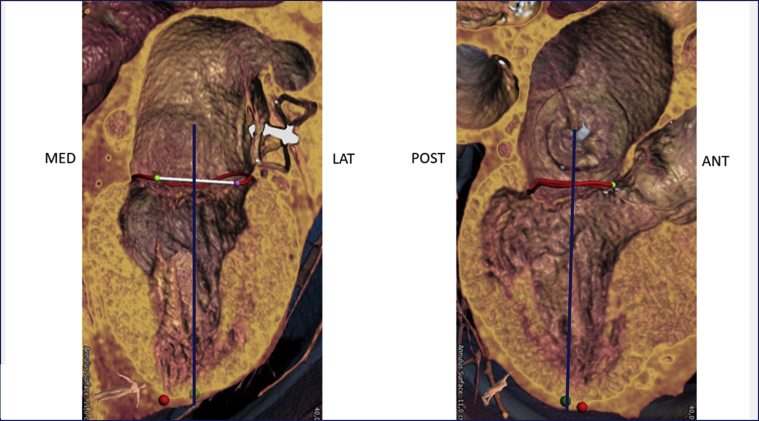

Echocardiography showed severe functional MR with a restricted and short posterior leaflet (MR ERO 0.11 cm2, dPmean 2 mm Hg). The aortic valve displayed severe insufficiency and mild stenosis. Multislice computed tomography (CT) imaging proved a suitable aortic valve anatomy for TAVR (perimeter 7.9 cm, diameter 25.2 mm, area 476 mm2, adequate coronary distance). Analysis of the mitral valve showed an ample estimated neo left ventricular outflow tract (>320 mm2 in systole and >400 mm2 in diastole) (Figure 1), an anterior-posterior distance of 31 mm, and an intercommisural distance of 42 mm allowing for approximately 15% oversizing using the 35M low-profile Tendyne valve. Simulation of TAVR implantation was not included. According to the scoring system proposed by Guerrero et al. (1), the patient had a MAC score of 3, mild calcification, most prominently with a sporn on the anterior-medial trigone (Figure 2). The suggested left ventricular apical access point for the TMVR deviated only 1 cm from the usual transapical TAVR access point, suggesting a favorable access for both the TMVR and the TAVR (Figure 3). Patient consent for publication of this case was obtained.

Figure 3.

Apical Access Point Prediction

The apical access point (green dot) is derived from 2 perpendicular axes through the mitral valve. In this patient the apical access point is slightly lateral and posterior from the true apex (red dot). Image courtesy of Abbott Vascular (Santa Clara, California).